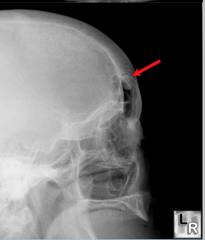

sialolith

-obstruction in the gland hard nodule in soft tissue at a salivary gland -calcification of material -can be seen radiographically